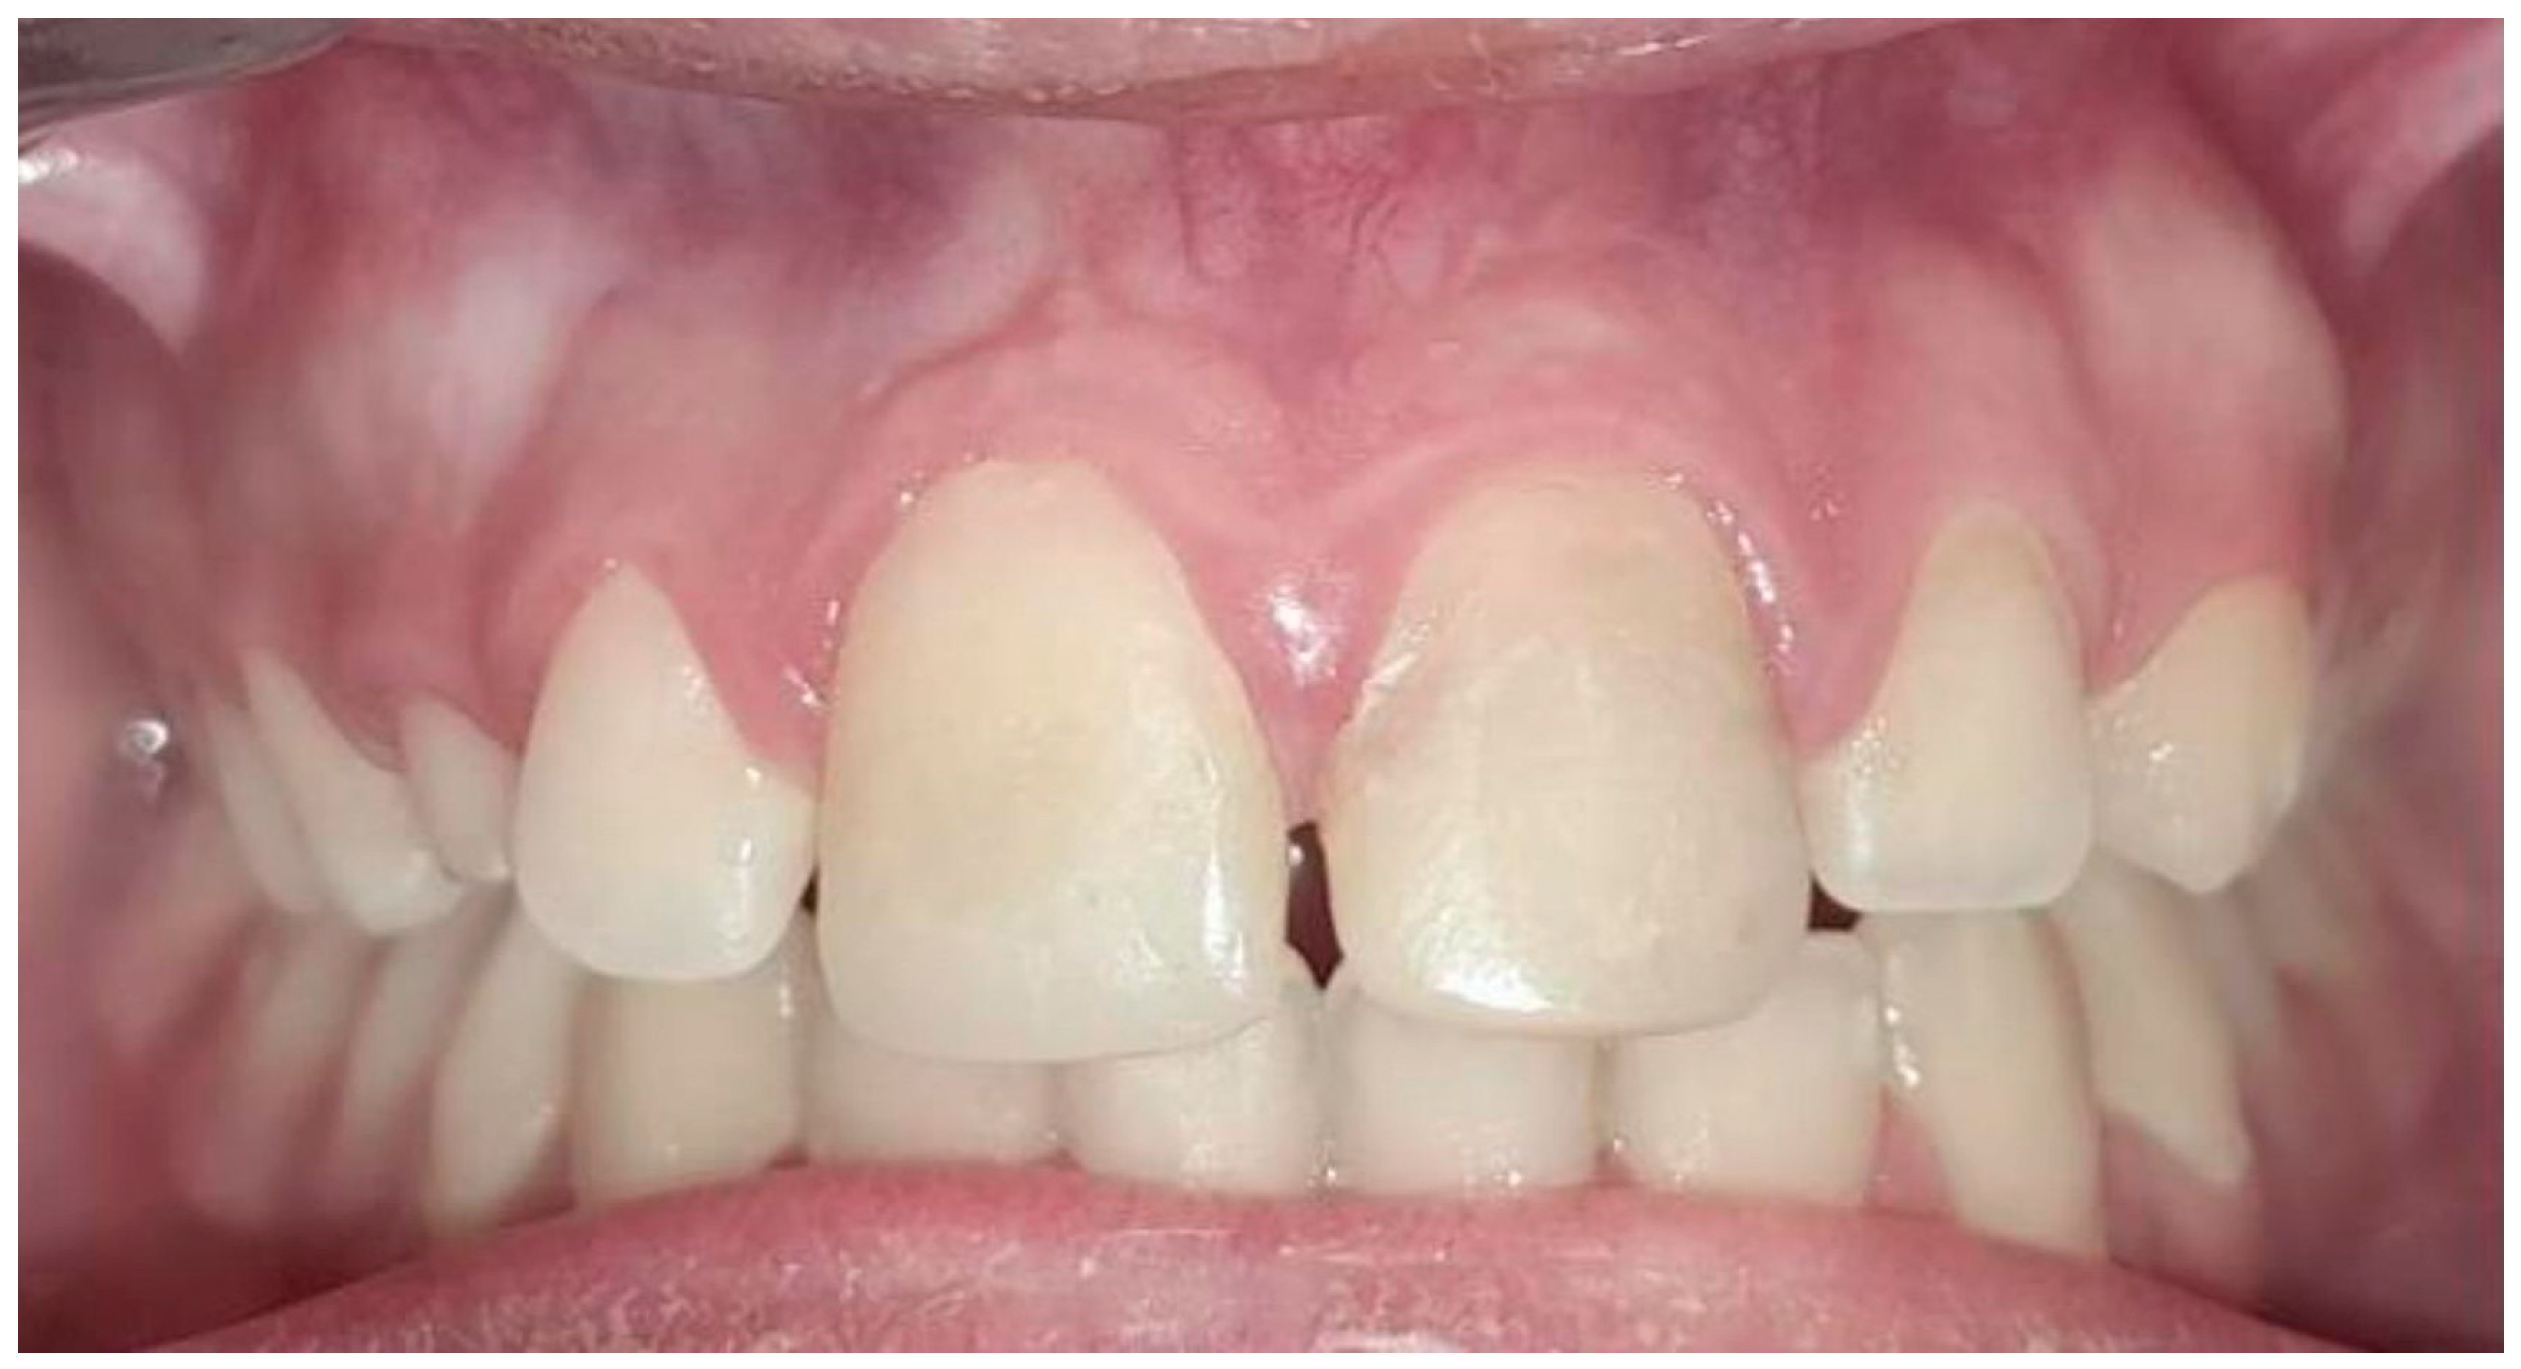

| Case 1 | 12 | 17% EDTA NaOCl | TAP | MTA | 3.7 mm | 2.2 mm | Calcified apical barrier |

| Case 2 | 11/21 | 17% EDTA NaOCl | Ca(OH)2 | BIODENTINE® | 3.1 mm/2.8 mm | 2.3 mm/2 mm | Calcified apical barrier |